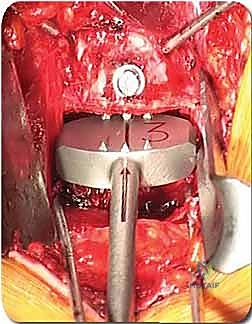

الخطوة 4: التحضير وزراعة القفص (Implant Insertion)

يتم قياس الفراغ المتبقي بدقة لاختيار الحجم المثالي للقفص الجراحي (Cage). يُصنع هذا القفص عادة من مادة PEEK أو التيتانيوم، ويتم حشوه بمادة عظمية (طعم عظمي ذاتي من المريض، أو طعم صناعي، أو بروتينات محفزة لنمو العظم BMP). يتم إدخال القفص بقوة في الفراغ، مما يؤدي فوراً إلى استعادة ارتفاع القرص الطبيعي وتوسيع المخارج العصبية (تخفيف الضغط غير المباشر).

الخطوة 5: التثبيت (Fixation)

لضمان أقصى درجات الثبات والسماح للعظم بالاندماج بمرور الوقت، يتم تثبيت القفص باستخدام شريحة معدنية صغيرة ومسامير من التيتانيوم تُثبت في الأجسام الفقرية من الأمام. في بعض الحالات، قد يرى الدكتور هطيف ضرورة إضافة تثبيت خلفي بمسامير عبر الجلد (Percutaneous Pedicle Screws) لزيادة الدعم.

الخطوة 3: إعادة بناء العمود الفقري (Reconstruction)

بعد إزالة الفقرة، يتبقى فراغ كبير جداً (Gap) في العمود الفقري. يجب سد هذا الفراغ لدعم وزن الجسم. يتم ذلك باستخدام:

* قفص قابل للتمدد (Expandable Cage): أسطوانة من التيتانيوم توضع في الفراغ ويتم توسيعها ميكانيكياً حتى تستقر بقوة بين الفقرة السليمة العلوية والسفلية.

* طعم عظمي هيكلي (Strut Graft): قطعة كبيرة من عظم بنك العظام يتم تشكيلها لتناسب الفراغ.

يتم حشو القفص بالطعوم العظمية لضمان الاندماج المستقبلي.

الخطوة 4: التثبيت القوي (Rigid Fixation)

نظراً لضخامة الفراغ الذي تم تعويضه، يتطلب الأمر تثبيتاً قوياً جداً. يتم استخدام شرائح تيتانيوم طويلة ومسامير من الأمام، وفي الغالبية العظمى من الحالات، يتطلب الأمر إجراء مرحلة ثانية لتثبيت العمود الفقري من الخلف بمسامير وقضبان لضمان استقرار البناء الجراحي بزاوية 360 درجة.